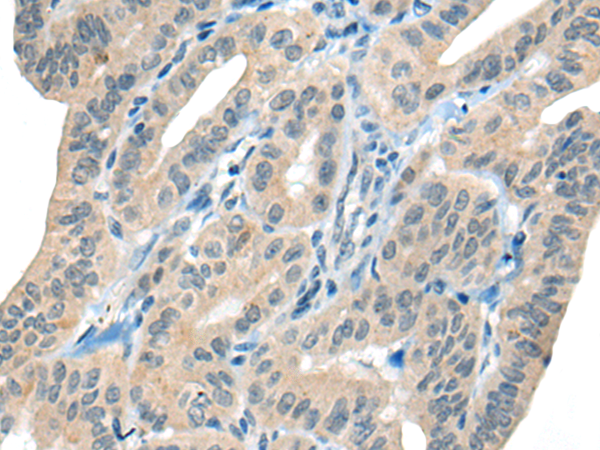

分类: 科研抗体货号: P07155别名: MN; CAIX应用: WB,IHC反应种属: Human